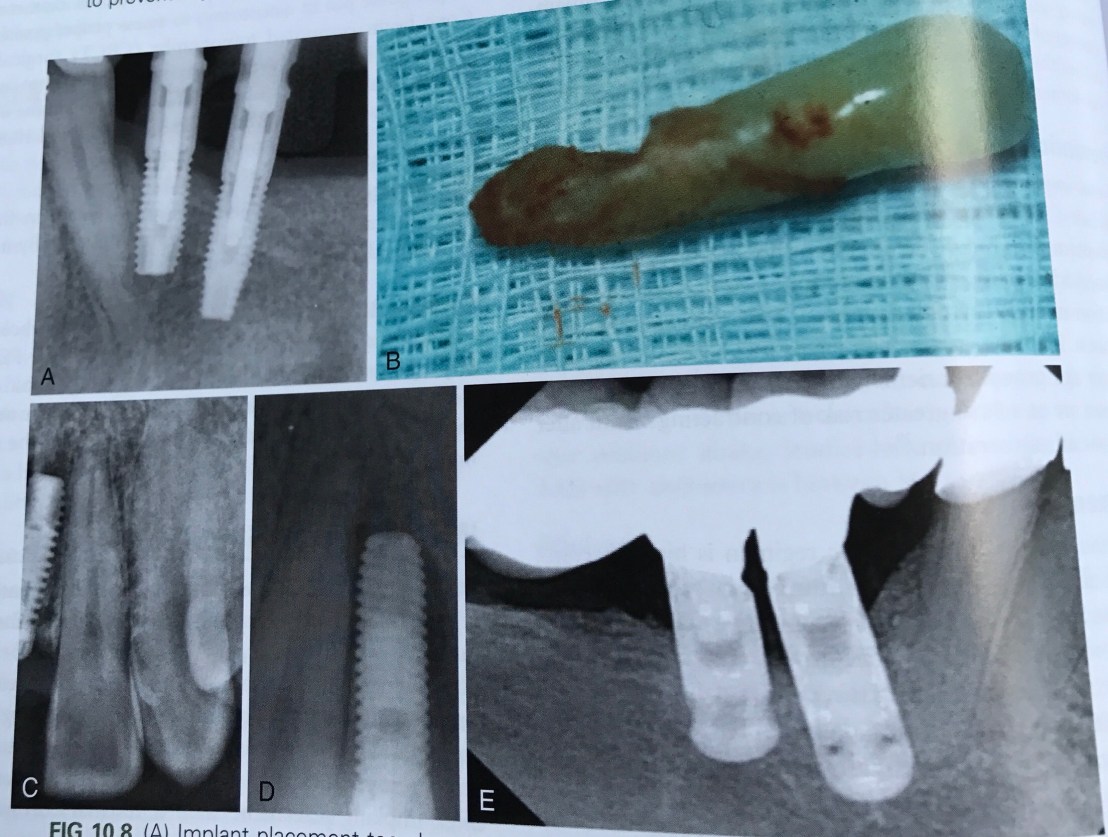

บทที่ 10 ข้อแทรกซ้อนหลัง Surgery

ในเคสที่ฝังแล้ว เกิดปัญหา Root proximity ที่มากเกินไป การ recall เป็นระยะหลังทำ เป็นสิ่งจำเป็นมาก เพราะอาจลงเอยด้วยการมี lesion และฟันตาย

Implant 14 มีการเคลื่อนตัวเข้าไปอยู่ใน Max. sinus

เคสนี้ก็ขยับ แต่เคลื่อนสูงขึ้นไปอีก คือไปที่ Cranial base เลย

แสดงสาเหตุที่ทำให้เกิดการ Displace 4 ประการ คือ

A Bone density คุณภายแย่มาก

B ต้องทำ Bone graft ก่อน แต่ไม่ทำ

D จาก Peri-implantitis

E ไม่มี bone support

การแก้ไข กรณีเคลื่อนเข้า sinus ครับ ใช้วิธีส่องกล้อง FESS (Fucntional Endoscopic Sinus Surgery)